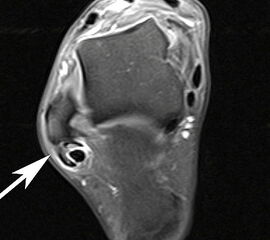

Ruptur der Peronaeus longus Sehne mit proximalisiertem Sehnenstumpf im MRT

Abbildung 14

Die akute vollständige Ruptur betrifft in der Mehrzahl der Fälle die Peronaeus longus Sehne, typischerweise in Höhe des Kuboid-Tunnels 40. Die Patienten berichten über ein geräuschvolles Reißen der Sehne mit anschließenden Schmerzen am lateralen Fußrand. Klinisch besteht eine Schwellung und Druckschmerzhaftigkeit im Sehnenverlauf. Die Plantarflexion und die Eversion des Fußes gegen Widerstand ist schmerzhaft 41. Bei einer kompletten Ruptur der Peronaeus longus Sehne kann es zu einem Ausriss des Os peronaeum kommen, dieses kann bis in Höhe des Außenknöchels dislozieren. Zur Beurteilung der Sehne ist das MRT mit Kontrastmittel das Verfahren der ersten Wahl.